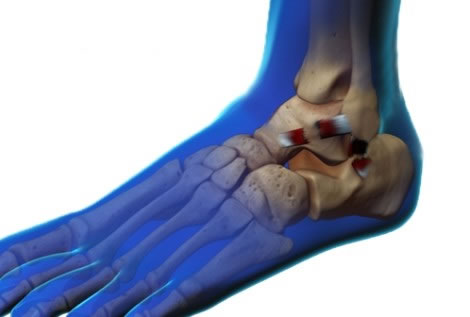

El tobillo es la articulación que conecta la pierna con el pie. En ella se relacionan tres huesos: tibia, peroné y astrágalo. Esta estructura ósea está fuertemente reforzada por músculos, tendones y potentes ligamentos que la estabilizan.